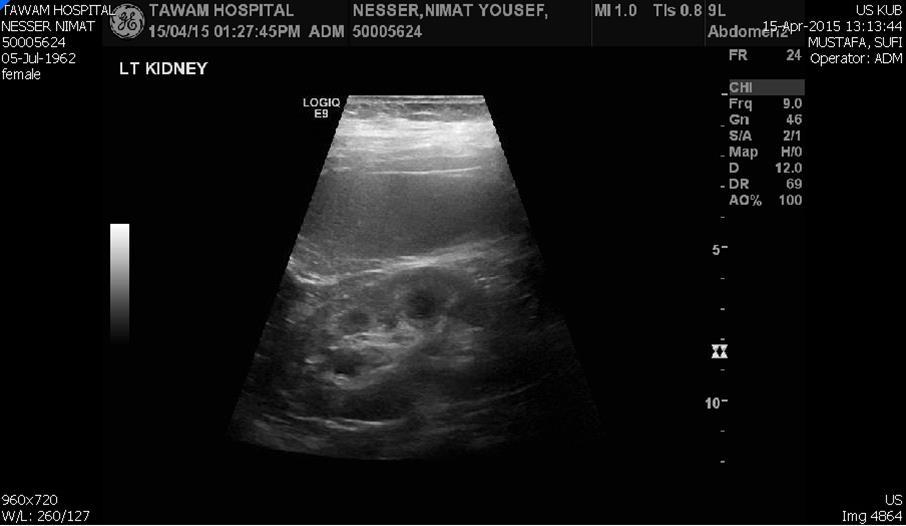

Blood tests on April 14th showed: Na = 131, K = 5.1, Urea = 6.9, S. Creatinine = 96, and eGFR = 61ml/min. Urine analysis and cultures confirmed E. coli urosepsis, blood cultures were negative. Renal US revealed echogenic kidneys, mild bilateral hydronephrosis of about 12 mm with normal ureters and urinary bladder (Figure 1 and Figure 2). Treatment with oral antibiotics resulted in improvement of temperature and dysuria. On April 20th patient seen by endocrinology and nephrology because of persistent back pain, dapagliflozin was discontinued and followed by resolution of symptoms in few days. Patient had two kidney ultrasounds in May and June, both indicated gradual resolution of bilateral hydronephrosis. Repeat CT of the abdomen on July 7th revealed complete resolution of hydronephrosis (Figure 3). Most recent eGFR is 72 ml/min.

Figure 2.Left kidney hydronephrosis

Left kidney hydronephrosis